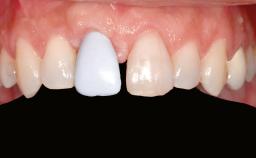

Ridge Preservation and Implant Placement for a Fixed Dental Prosthesis After a Car Accident

Prosthesis Type FDP